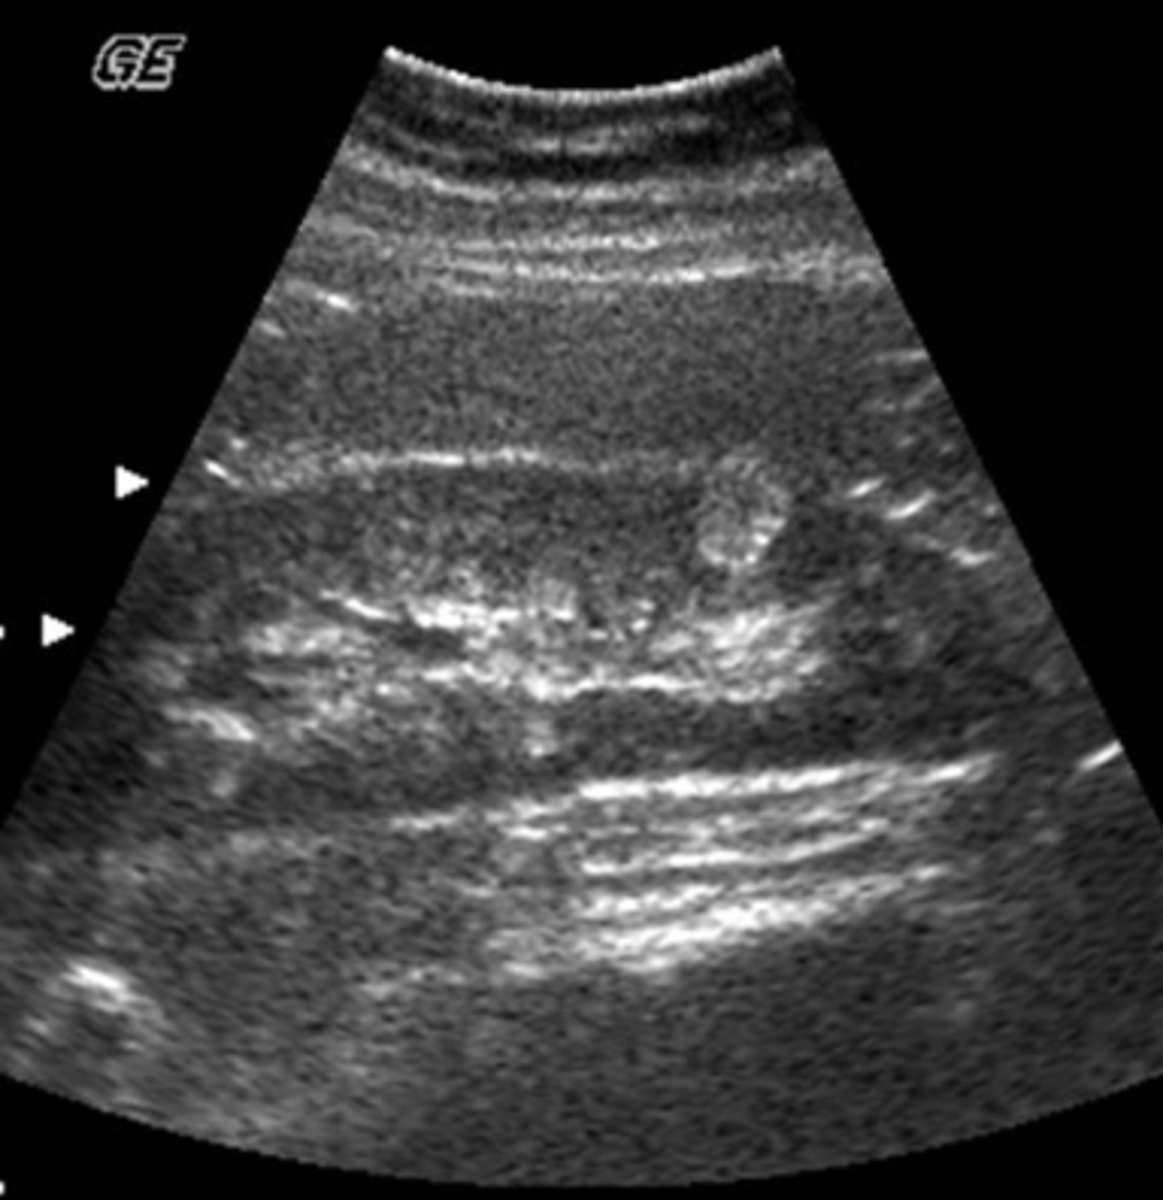

b. splenic and retroperitoneal varices

A 49-year-old male presented with a clinical history of liver cirrhosis and portal hypertension. In the transverse image below, multiple hypoechoic structures are seen at the splenic hilum and between the kidney and spleen. What is the most likely etiology of these structures.

a. multiple aneurysms of the splenic artery

c. loculated ascites

d. polycystic kidney disease

e. fluid-filled loops of bowel